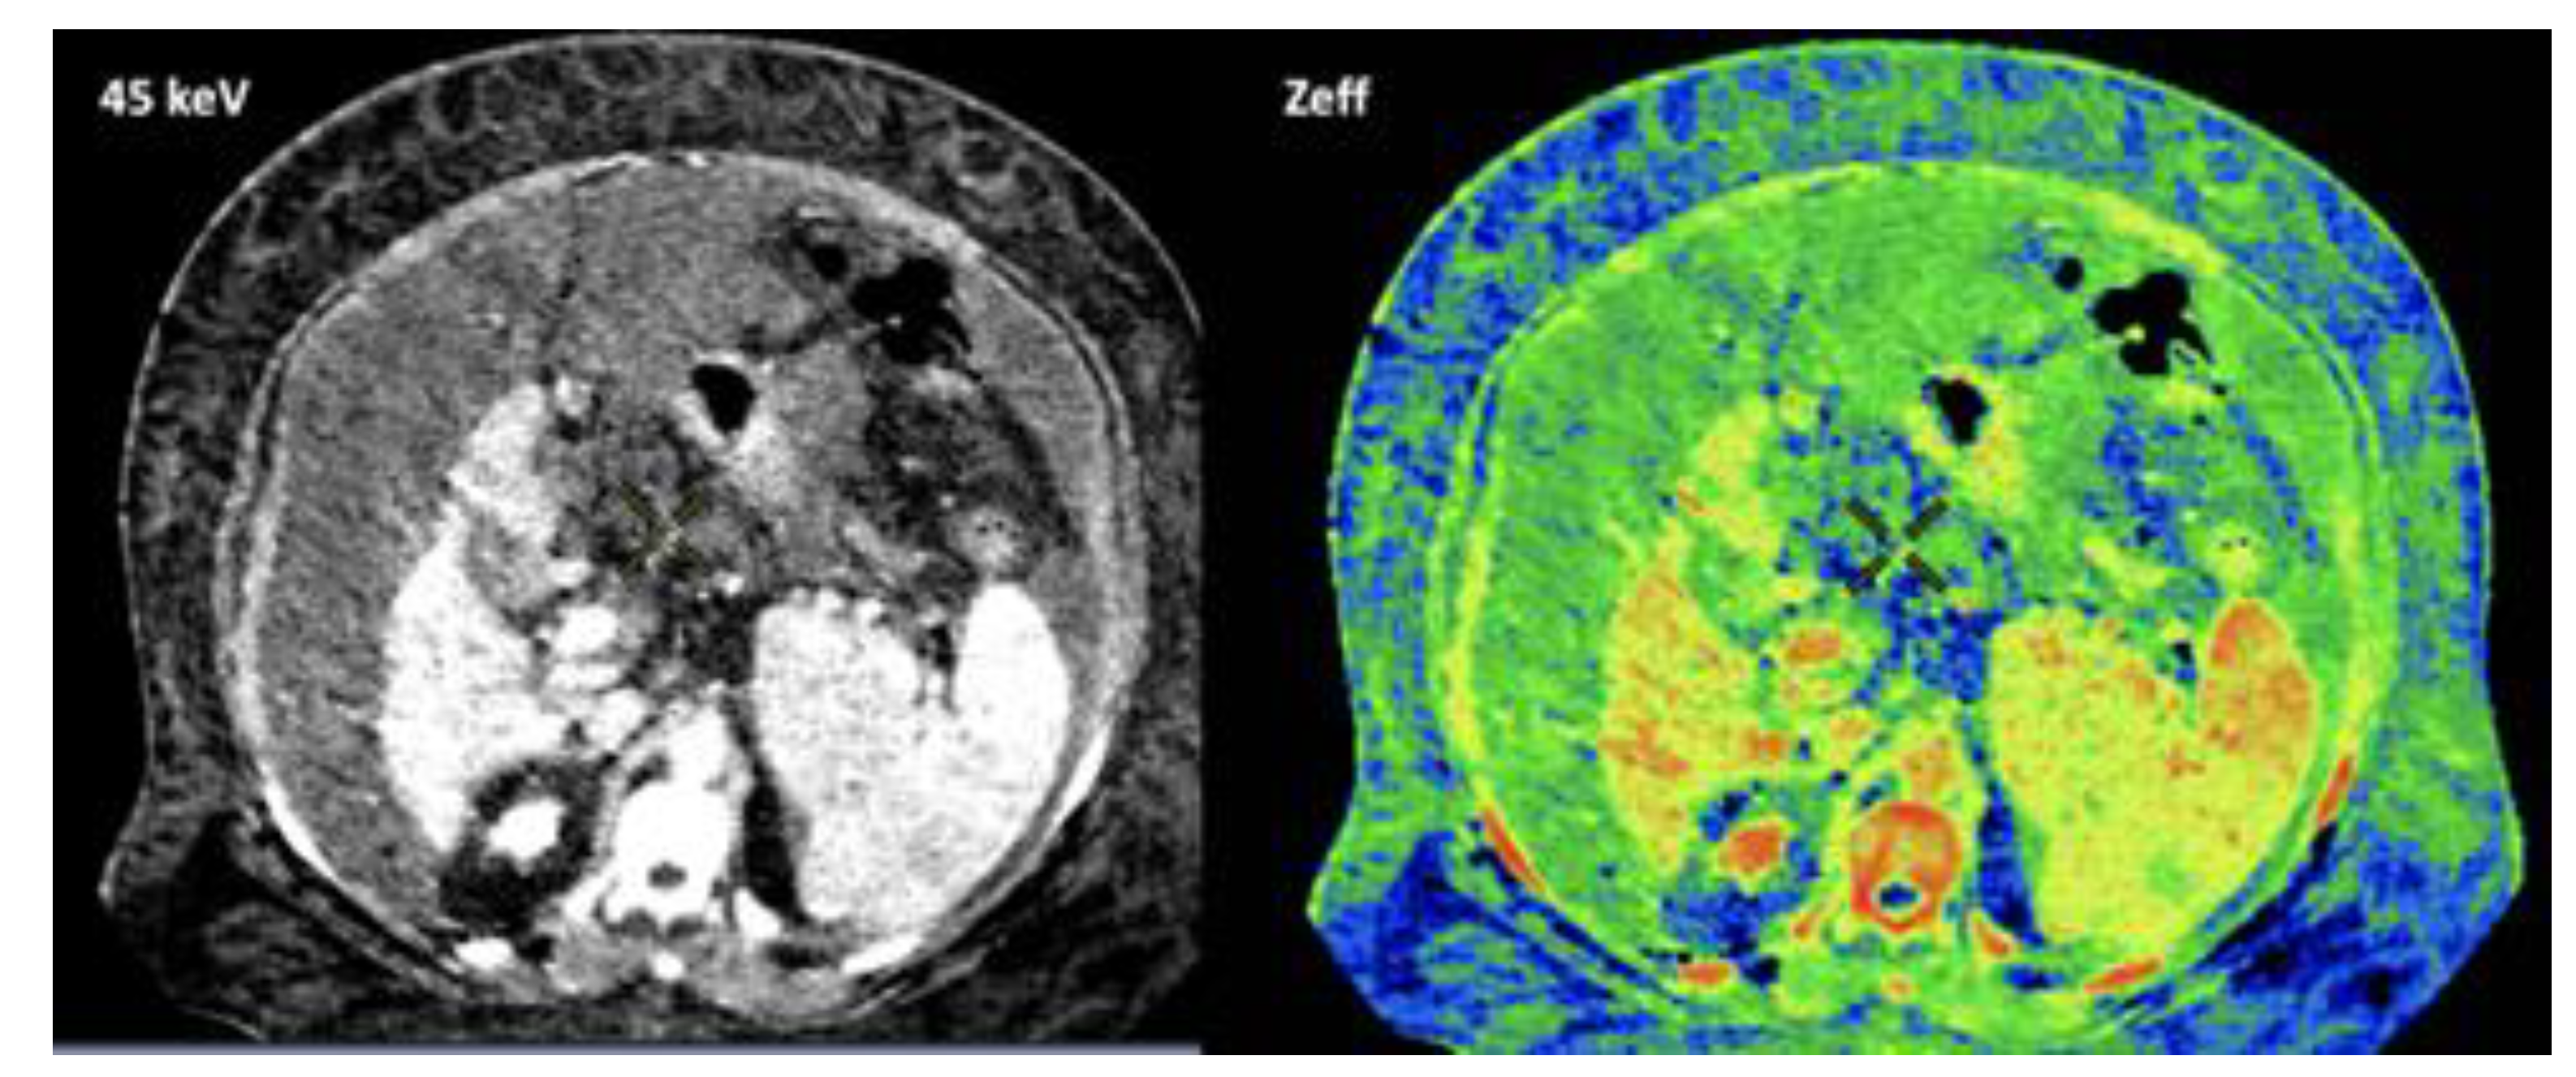

- Mileto, A.; Allen, B.C.; Pietryga, J.A.; Farjat, A.E.; Zarzour, J.G.; Bellini, D.; Ebner, L.; Morgan, D.E. Characterization of Incidental Renal Mass With Dual-Energy CT: Diagnostic Accuracy of Effective Atomic Number Maps for Discriminating Nonenhancing Cysts From Enhancing Masses. Am. J. Roentgenol. 2017, 209, W221–W230. [Google Scholar] [CrossRef] [PubMed]